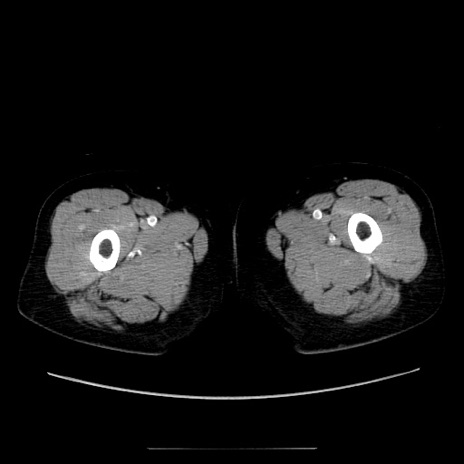

症例5(横断像)

【症例】70歳代女性

【主訴】お腹が張る

【現病歴】1週間くらい前から腹部膨満の自覚あり。昨日夜から増悪したため、本日救急外来受診。

【身体所見】意識清明、BT 36.5℃、BP 165/106mmHg、HR 80bpm、SpO2 98%、腹部:膨満、軟、自発痛・圧痛なし、触診にて不快感あり、腸蠕動音:減弱

【データ】WBC 12600、CRP 1.04